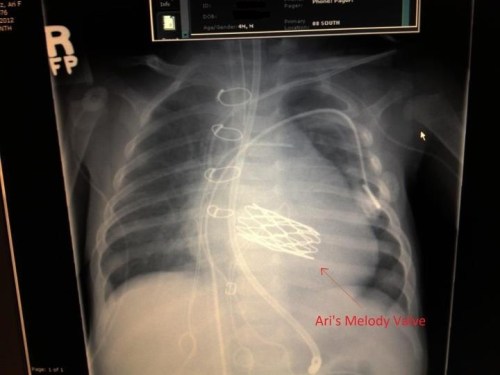

And here’s his chest x-ray.

The big honeycomb thing in the middle is that valve. Check out that bad boy.